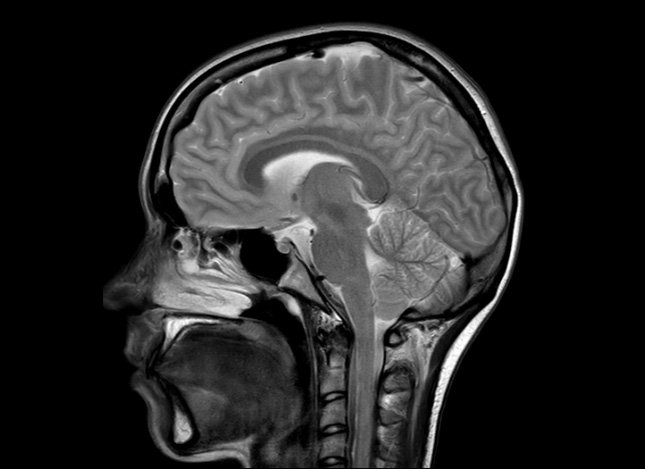

Die Magnetresonanztomographie oder auch Kernspintomographie (MRT) ist ein modernes und seit vielen Jahren etabliertes Schnittbildverfahren zur Untersuchung aller Körperregionen. Um ein Bild zu erzeugen, werden hierbei keine Röntgenstrahlen, sondern ein starkes Magnetfeld eingesetzt, das eine hohe räumliche Auflösung und exzellente Kontrastdarstellung möglich macht.

- Kopf, Gehirn, Rückenmark